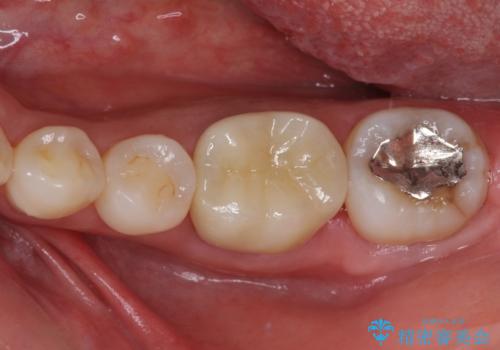

- 左下奥に、咬んだときの痛みを感じて来院された患者様です。

排膿路が形成されている歯は既に失活しており、根管治療が必要になっていました。

根管治療などを行った後に、オールセラミッククラウンにて補綴することとしました。